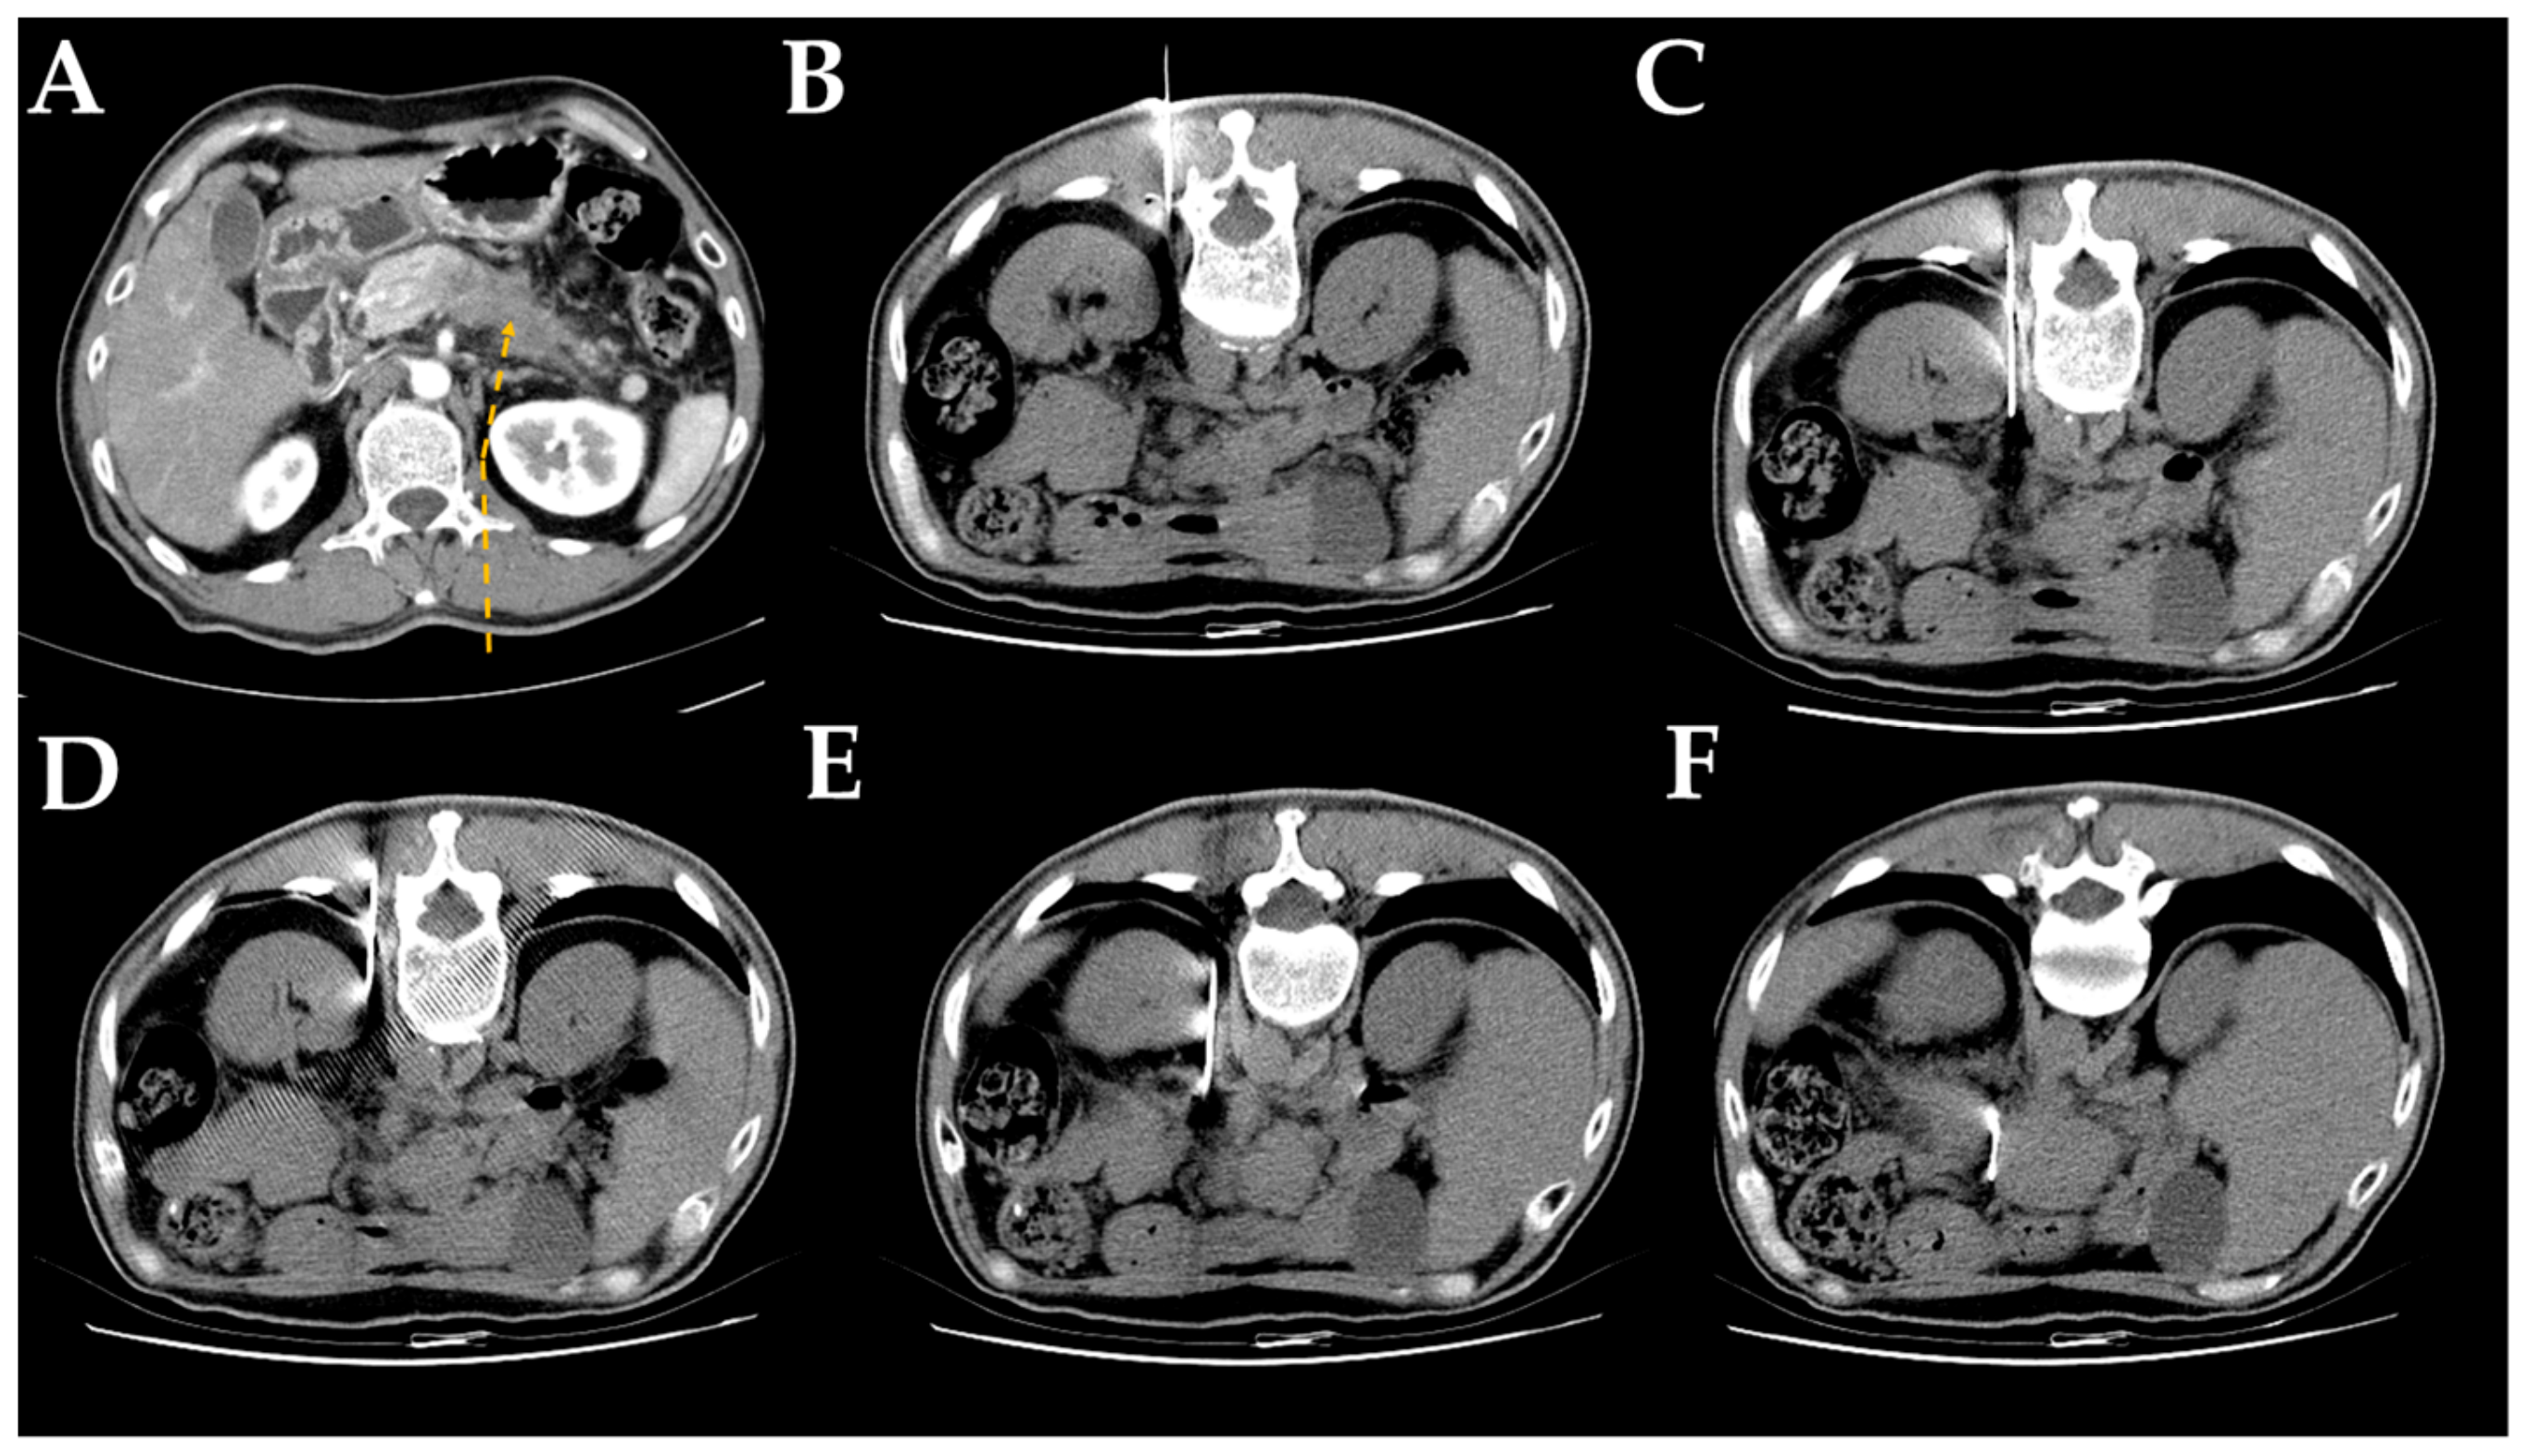

2.2. Computed Tomography-Guided Core Needle Biopsy Technique

| Detour route 1 | 169 | 29 (14–54) |

| Detour route 2 | 169 | 28 (12–51) |

| Detour route 3 | 26 | 28.5 (17–42) |

| Detour route 4 | 19 | 29 (16–41) |

| Detour route 5 | 26 | 29.5 (19–40) |

| Detour route 6 | 11 | 28 (19–38) |

| Head | 37 | 71 | 46 | 59 | 213 (50.7%) |

| Body | 6 | 27 | 38 | 59 | 130 (31.0%) |

| Tail | 4 | 5 | 15 | 53 | 77 (18.3%) |

| Detour route 1 | 26 | 49 | 43 | 51 | 169 (40.2%) |

| Detour route 2 | 16 | 32 | 39 | 82 | 169 (40.2%) |

| Detour route 3 | 2 | 4 | 3 | 17 | 26 (6.2%) |

| Detour route 4 | 0 | 2 | 6 | 11 | 19 (4.5%) |

| Detour route 5 | 3 | 10 | 6 | 7 | 26 (6.2%) |

| Detour route 6 | 0 | 6 | 2 | 3 | 11 (2.6%) |